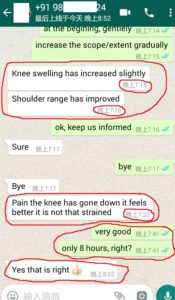

1. The Gentleman in Kenya started his treatment at his home April 27, now he said: (will update his more progresses soon)